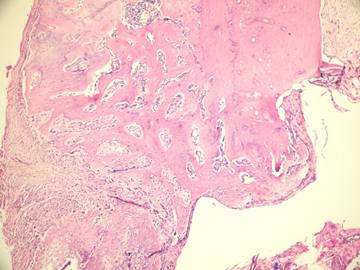

Figure 6

Inflammatory cells and new bone formation in control group (without irrigation, H&E

In the present study we evaluated the specimens in terms of new bone formation, presence of infection, necrosis and fibrosis Our study demonstrated significant difference regarding the necrosis values between control group (without irrigation) and the group irrigated with 25°C and 4°C saline (Figures 4-6). Necrosis was not observed in second and third groups. However copious saline irrigation was useful for cleaning the operation area from any remnants of the drill. It is thought that this can be an advantage for wound healing.

Although there was no statistically significant difference between the group irrigated with 25°C and 4°C saline for new bone formation, latter group had numerous osteoblasts and more prominent osteoblastic rim around the trabeculae of new bone (Figures 4,5). These results indicate that there is no disadvantage to use 25°C saline irrigation, but it may be better to use 4°C saline irrigation for rapid healing.